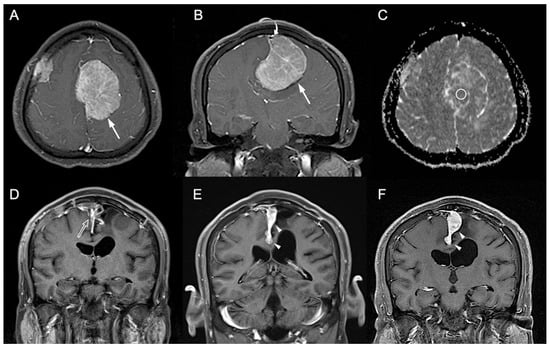

3.1. Clinical and Imaging Findings